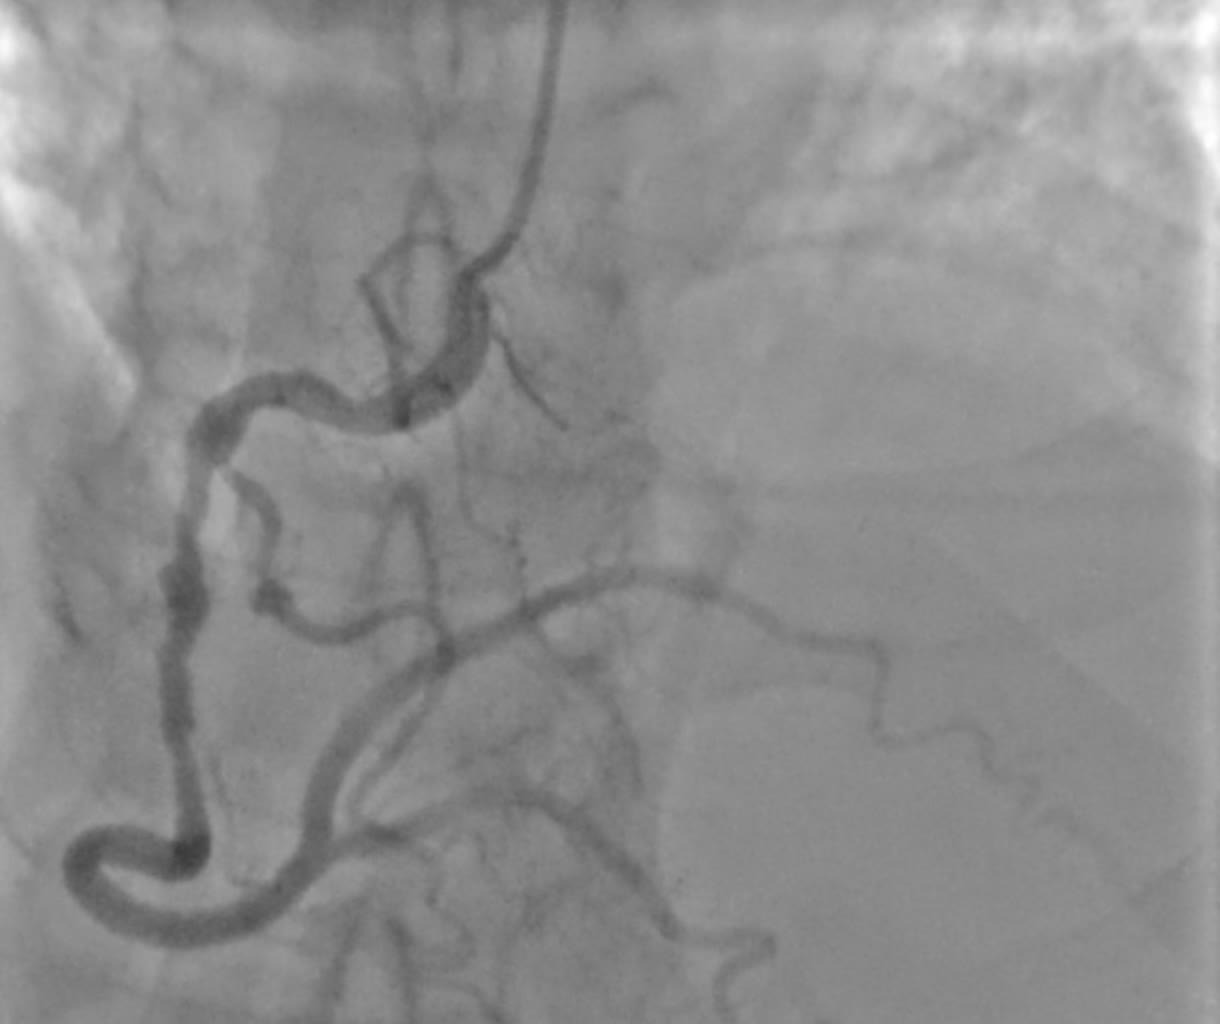

W pracowni radiologii zabiegowej Szpitala Specjalistycznego Ducha Świętego w Sandomierzu wykonano prekursorski zabieg z użyciem minimalnej objętości kontrastu w trakcie angioplastyki wieńcowej czyli naprawy zwężeń w tętnicach wieńcowych u pacjenta z chorobą wieńcową. W zabiegu brali udział lekarze Michał Tarnowski, Mateusz Wiśniowski, Paweł Konrad i dr n. med. Piotr Wańczura.

Zabiegi takie wykonuje niewiele ośrodków. Pomagają one ochronić pacjentów jeżeli chodzi o uszkodzenie funkcji nerek.

Fot. Szpital Specjalistyczny Ducha Św. w Sandomierzu/Facebook